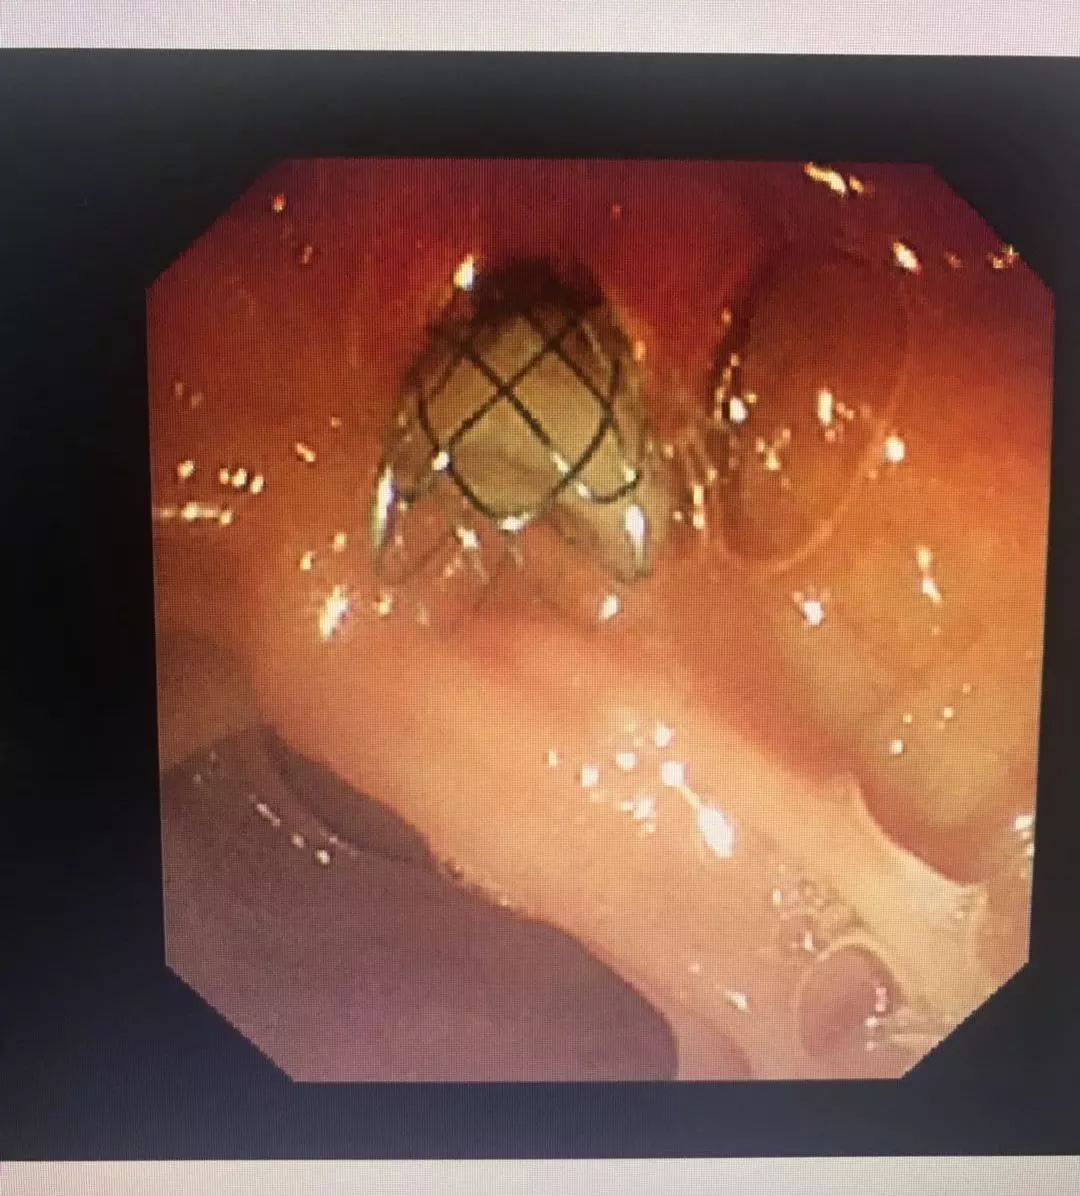

内镜示:肠内支架引流脓性胆汁

术中进镜困难、插管方向及切开方向变化等等困难均被一一克服,看着棕黑色的胆汁顺利流入肠道,术中的担忧、紧张,均被成功冲散。患者术后退黄明显,术后第二天白细胞下降至正常水平,退烧,可以进流质饮食,手术效果非常明显,5天后即康复出院。